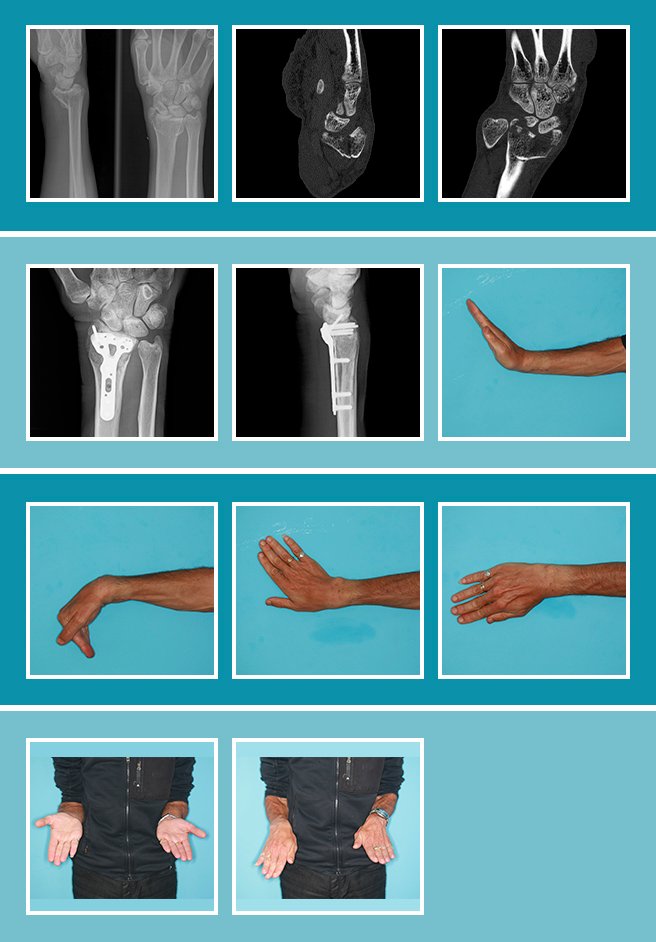

Caso real 1:

La estabilidad del esqueleto óseo de la muñeca, al igual que en la mano, es condición “sine qua non” para poder realizar todos los movimientos con fuerza y precisión. Cualquier fractura mal reducida o mal consolidada supone una pérdida de función global de la muñeca que, en función del hueso afecto, puede conllevar importantes déficits funcionales.

Las fracturas de la muñeca requieren una valoración precisa y, si son quirúrgicas, una reducción anatómica, osteosíntesis y movilización precoz. Solo así podemos obtener resultados satisfactorios